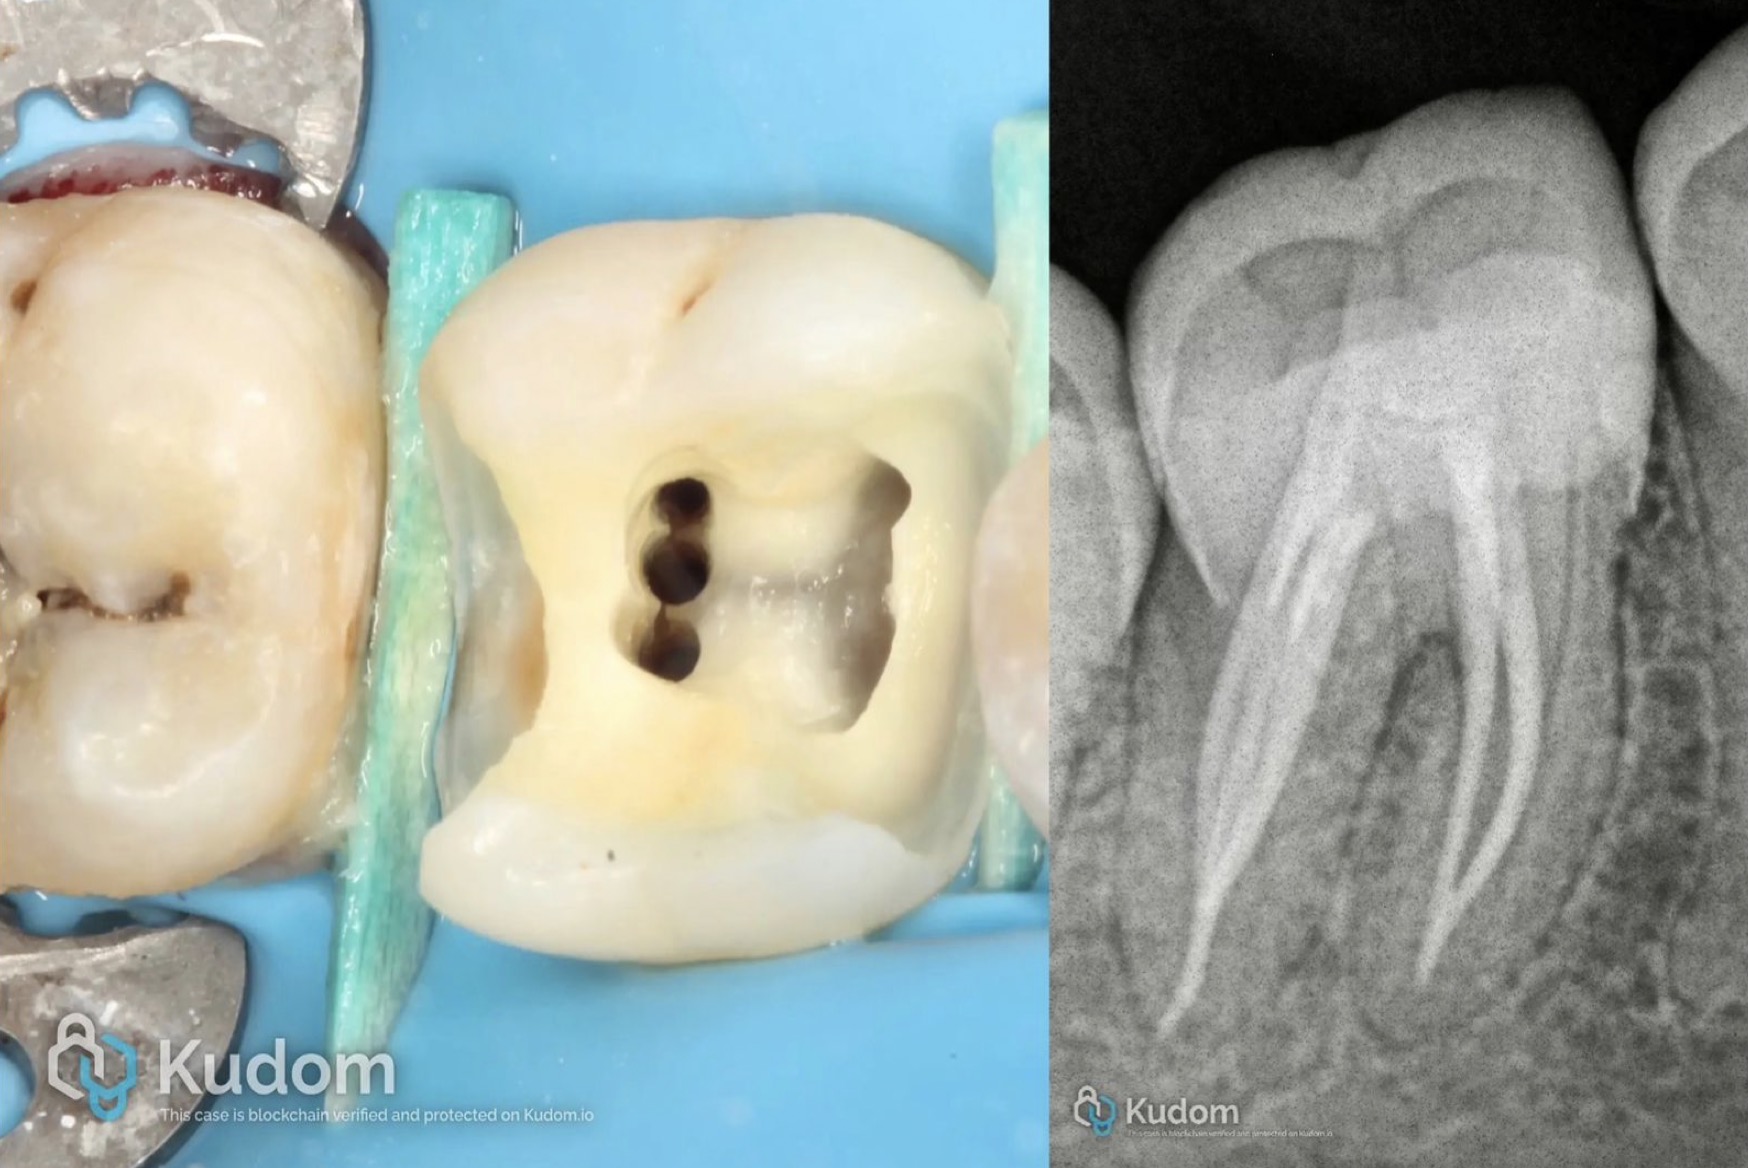

Advances in endodontic materials have influenced contemporary approaches to root canal obturation. A bioceramic sealers possess favorable properties, including biocompatibility, dimensional stability and the ability to form hydroxyapatite, which may enhance sealing root canal spaces. These characteristics have contributed to a shift toward simplified obturation techniques, particularly the single-cone approach. Compared with traditional compaction techniques, this method reduces procedural complexity and clinical time while maintaining an effective seal of the root canal system. For straightforward endodontic cases with adequate cleaning and shaping, simplified obturation protocols using bioceramic sealers have demonstrated predictable clinical outcomes.